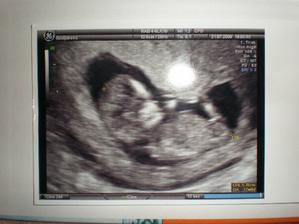

Když si ze mě náš tatínek dělal legraci že vypadám těhotná, řekla jsem si, že je fajn že se na to tak těší, ale já se cítila spíš nemocně než těhotně. Když zdánlivá nemoc ustoupila, ale lesklé oči zůstaly, moje kamarádka co mi utekla až do Dánska si ze mě na skypu dělala legraci a já si z hecu opravdu udělala testík. OUHA to překvápko. Čárka vyjela jako by ji někdo maloval fixou. A já si řekla spíš "a sakra" než jupiii. Večer dostal do ruky tatínek do jedné ruky testík a do druhé návod na rozluštění... Chvíli to trvalo, tak jsem aspoň měla čas si připravit co řeknu. Byl z toho na rozpacích, ale měl radost, možná větší než já 😀 . Moc se mi tomu nechtělo věřit a tak jsem odpoledne ceou proceduru zopakovala za taťkovy asistence a výsledek byl překvapivě ještě víc vidět než na prvním testíku. Další den mi to nedalo a já udělala mininákup v lékárně... výsledek nezvratný. Objednala jsem se k dr. a za další dva dny jsem držela v rukách první prcóóóóóchovu fotku 🙂

21. 7. 09 Návštěva dr. Poláka v jeho ordinace. Čekání nekonečné, spousta lidí, spousta bříšek. Ale po návštěvě WC taky spousta slz a strachu, protože jsem po cestě začala krvácet přímo v čekárně. Sestřičce oznámeno že krvácím, posadila mě zpět do čekárny. Myslela jsem že se zblázním, byla to zatím nejdelší hodina v mém životě. Na Uz pan doktor prohlásil že "miminko vypadá zdravě". Pak se snažil najít srdíčko, a když to po chvíli vzdal, řekl jenom: "není vidět srdíčko, je schované, ale je tam". Lehce znechucená že jsem vlastně srdíčko ani neviděla a po velmi kusých informacích, že mimi odpovídá týdnu 12+1dle CRL, jsem po cca 5 min. odešla. Dalším zážitkem bylo placení. Po estempóre při placení jsme dostali konečně fotečku z velkého UZ a tam na nás vykouklo naše miminko. Když jsme přijeli domů, sesypaly se na nás babičky a začaly sázky na pohlaví miminka, které však ještě sami nevíme 😀